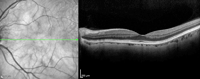

Figura 1. Adhesión vitreomacular.

Figura 2. Tracción vitreomacular.

Figura 3. Tracción vitreofoveolar.

Figura 4. Tracción vitreofoveolar "en meseta".